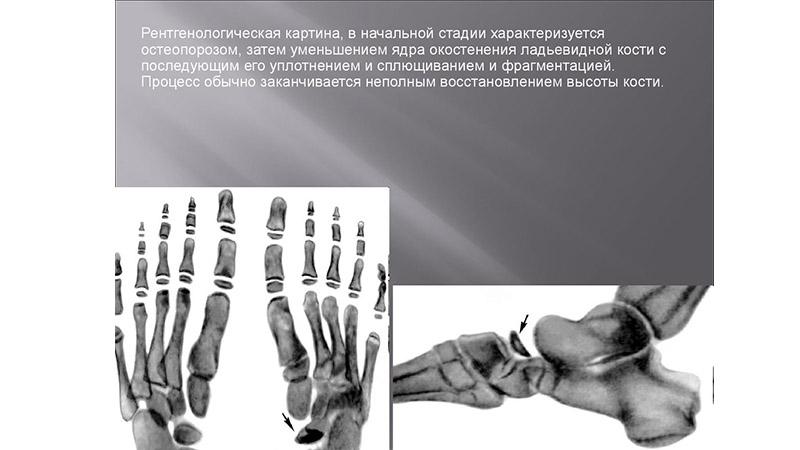

Болезнь Келлера I, также известная как остеохондропатия ладьевидной кости стопы, чаще всего встречается у мальчиков до 7 лет. Это заболевание может затрагивать одну или обе ноги и проявляется болями на тыльной стороне стопы, а также отеками. В процессе болезни ребенок может хромать и стараться не нагружать больную ногу, однако через год начинается восстановление кости, и дискомфорт исчезает.